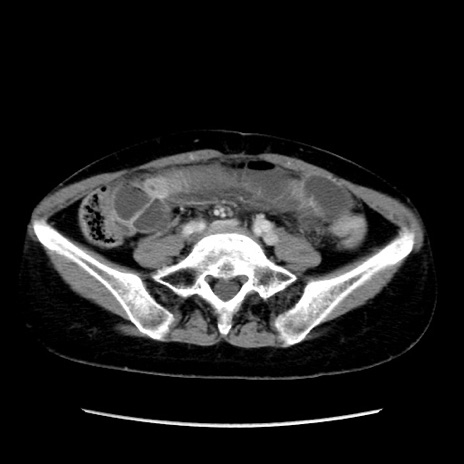

症例32(横断像)

【症例】40歳代 女性

【主訴】上腹部痛、嘔気・嘔吐

【現病歴】約9時間前頃から急に上腹部痛、嘔気、嘔吐が出現。改善しないため救急要請。

【既往歴】子宮頚癌(広汎子宮全摘術、放射線療法)、腸閉塞

【身体所見】腹部:平坦、軟、腸雑音亢進、上腹部を中心に腹部全体に圧痛あり。

【データ】WBC 8400、CRP 0.03